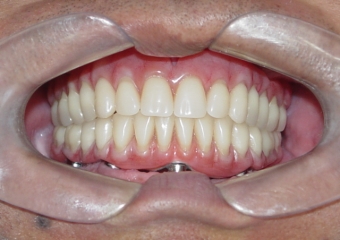

Prótese fixa inferior em resina

Sorriso final, do caso terminado em setembro de 2008